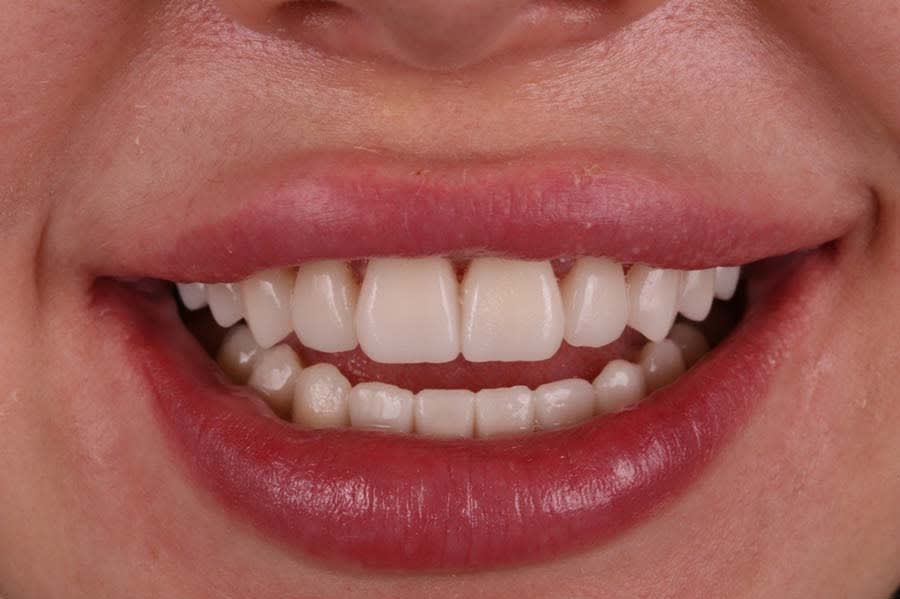

Treatment eliminated the anterior open bite, restored functional occlusion, and achieved harmonious esthetics matching the approved design (Figure 14). Final restorations showed precise proximal contacts and stable margins and required no occlusal adjustments. The multilayered lithium-disilicate restorations closely replicated natural teeth in form, color, and light dynamics.11

The esthetic result achieved anterior tooth symmetry, correct midline position, shape and proportion consistent with the approved wax-up, and individual effects like opalescence, incisal translucency, and natural halo. The patient reported significant improvement in smile esthetics, increased social confidence, and functional satisfaction. Clinical documentation confirmed no inflammatory changes at the gingival margin, stable soft tissues along the prosthetic structures, and preserved papilla height.

At 1-year follow-up, the gingival contour remained stable with no inflammation, recession, or discoloration of restorations. The long-term stability of the esthetics and function reflected the quality of the material choices and protocol adherence.13 Functional parameters were maintained, including no occlusal interferences, stable CR, and balanced lateral contacts. The patient continued using a custom nightguard to prevent potential parafunctional forces. The esthetic result, which remained unchanged after a year, demonstrated restoration durability, biocompatibility, and an effective protocol.

Final photographs showed smile harmony, optimal anterior tooth display, symmetry, and balanced soft- and hard-tissue relationships (Figure 15). The achieved outcome aligned with the initial clinical and esthetic goals and required no further corrections. The case demonstrated successful management of a complex open-bite rehabilitation through a multidisciplinary approach, digital modeling, and integrated functional diagnostics.